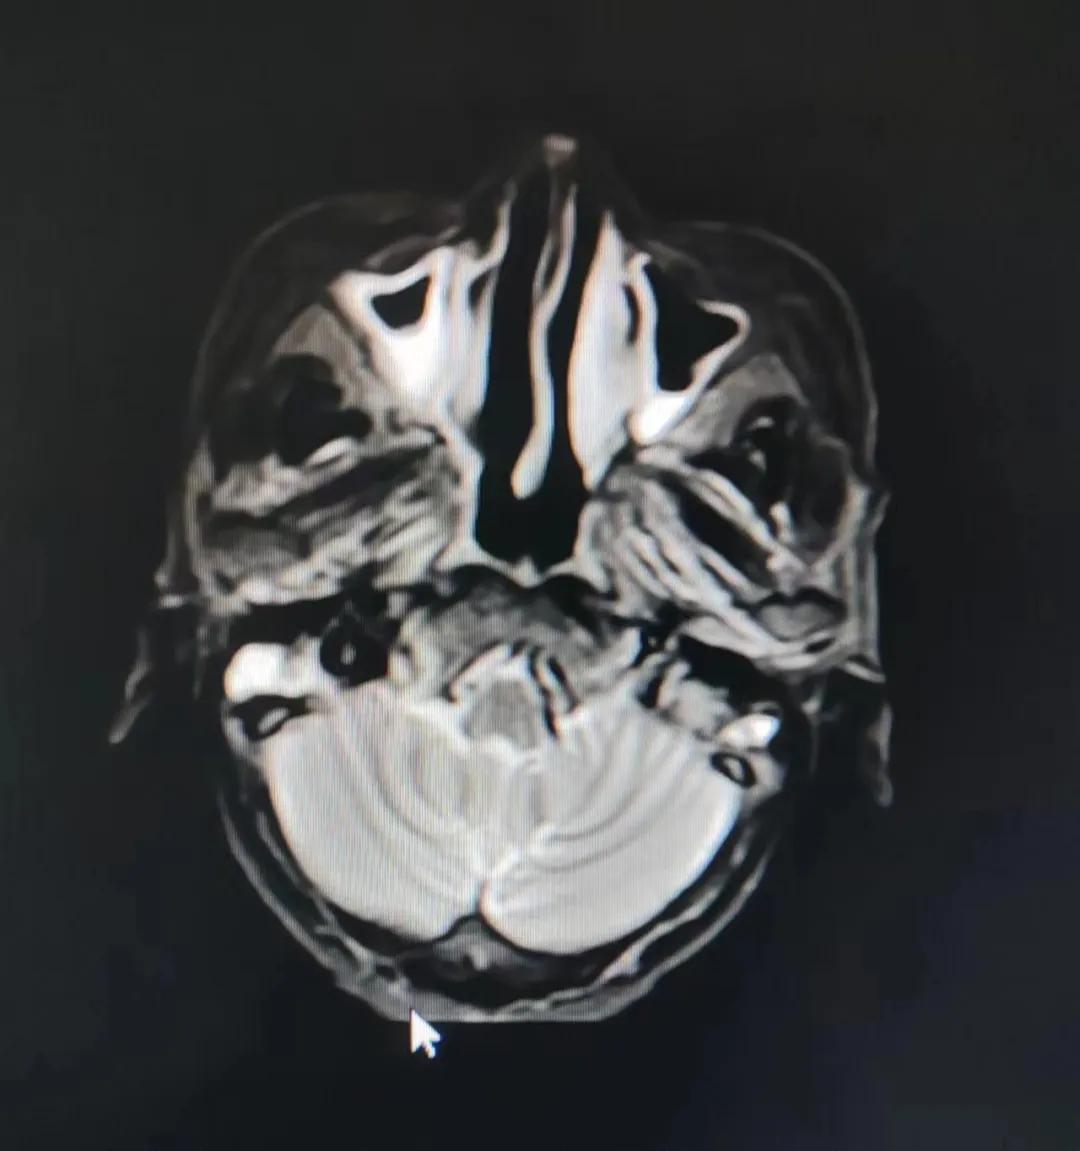

治療前

考慮到患者年齡較大、體質(zhì)差,手術(shù)難度大,且常規(guī)的放射治療難以保護(hù)患者晶體造成患者雙眼視力損傷,放療團(tuán)隊(duì)以最快的速度制定了精準(zhǔn)放射治療方案并開(kāi)始為其實(shí)施治療。僅僅數(shù)日后,老人腫塊出血即得到控制,腫塊明顯縮小,放療20次后腫塊迅速縮?。?/div>